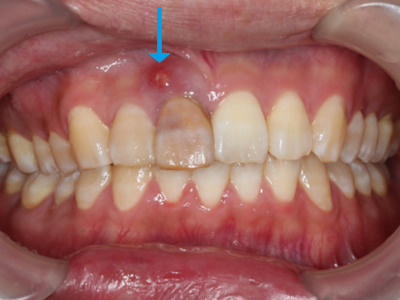

前歯が腫れてしまったと来院された患者様です。

レントゲンを見てみると歯根(歯の根の部分)が黒く溶けていることが分かり、抜歯と診断しました。

前歯のインプラントはとても難しく技術がないと歯茎が下がってしまったりと不具合が出てしまいます。

X-ray

処置後、非常に審美的な補綴物が入ったことが分かるかと思います。